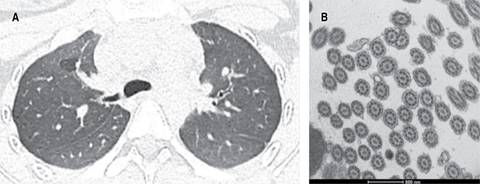

Caso 2: femenino de 16 años, con infecciones respiratorias de repetición desde los tres años, tratada previamente por asma de difícil control, todas sus espirometrías con obstrucción leve sin respuesta a broncodilatador; se realizó abordaje por la persistencia de la sintomatología respiratoria (tos productiva, abundantes secreciones en vía aérea y cuadros de sibilancias recurrentes). TACAR con presencia de bronquiectasias cilíndricas (Figura 2A). Se realizó broncoscopia flexible con toma de biopsia endobronquial para microscopia electrónica, en la cual se reportan cambios compatibles con DCP tipo V de la clasificación de Barlocco y colaboradores,8 correspondientes a fusión ciliar (Figura 2B). Se solicita panel genético de ciliopatías, el cual señala deleción heterocigota del cromosoma 16p12.2 variante patogénica (Figura 2C). Se inició terapia de rehabilitación pulmonar, se disminuyó dosis de inhaladores hasta el retiro, con mejoría de los síntomas respiratorios. Actualmente sólo se encuentra con fisioterapia pulmonar. Se inició manejo multidisciplinario a través de los servicios de genética, cardiología y otorrinolaringología. Se descartó situs inversus.

Figura 2: A) Corte axial de tomografía computarizada de alta resolución en la cual se observa imagen de bronquiectasia cilíndrica en pulmón derecho y engrosamientos peribronquiales en pulmón izquierdo; microscopia electrónica (B), en la cual se reportan cambios compatibles con discinesia ciliar primaria tipo V de la clasificación de Barlocco et al.,8 correspondientes a fusión ciliar; panel genético (C) de ciliopatías con deleción heterocigota del cromosoma 16p12.2 variante patogénica. CNV = variación del número de copias.